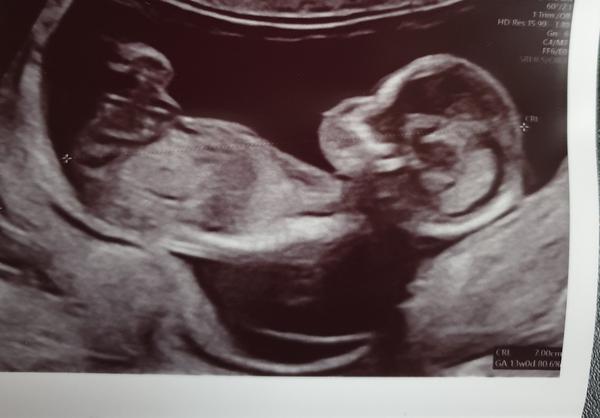

poznal byste pohlaví miminka?

Fotky jsou ze screeningu v trimestru a stáří miminka je 13+0.